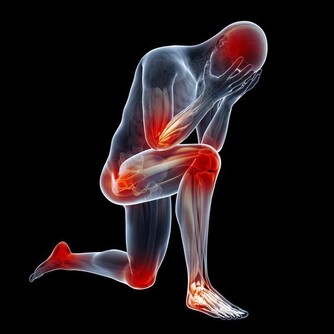

髕骨軟骨軟化的症狀

疼:上下樓會痛,膝關節突然打軟無力。有時候是半蹲發力時疼,尤其是搬重物的時候。嚴重的日常生活的活動中就會疼,走路的時候都有膝關節打軟腿的現象。另外,如果用手按摩髕骨的邊緣,常常有明顯壓痛。

響:膝關節屈、伸活動時,髕骨下面常常會出現響聲,嚴重的患者,自己坐著伸直腿,把手放在髕骨上,壓著髕骨摩擦一下,就能聽到“沙沙”的響聲,像關節裡面有沙子一樣。

腫:因為關節內部的炎症,導致關節滑膜分泌出很多液體,所以表現出膝關節腫脹。

細:髕骨軟化,會導致股四頭肌肌肉萎縮,疲軟、所以大腿外觀會變細。